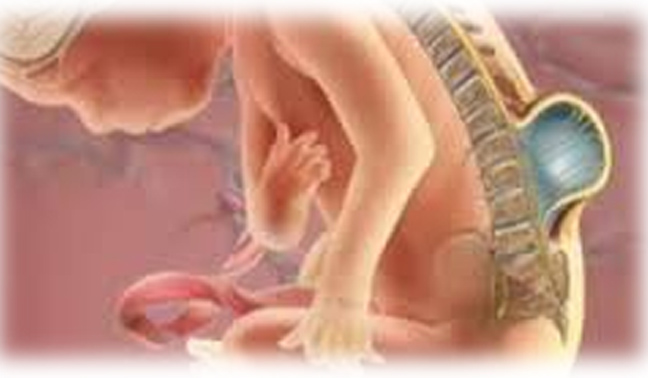

Η ανεπάρκεια αυτή σύγκλεισης δεν δημιουργεί προβλήματα παρά σπανιότατα, όταν πραγματικά δεν συμπληρώνεται η σύγκλειση του δακτυλίου σε μεγάλη έκταση, οπότε προβάλλει ο νωτιαίος σάκκος κάτω από το δέρμα και νεογέννητο εμφανίζει κινητικά προβλήματα. Τότε λέγεται μηνιγγοκήλη.